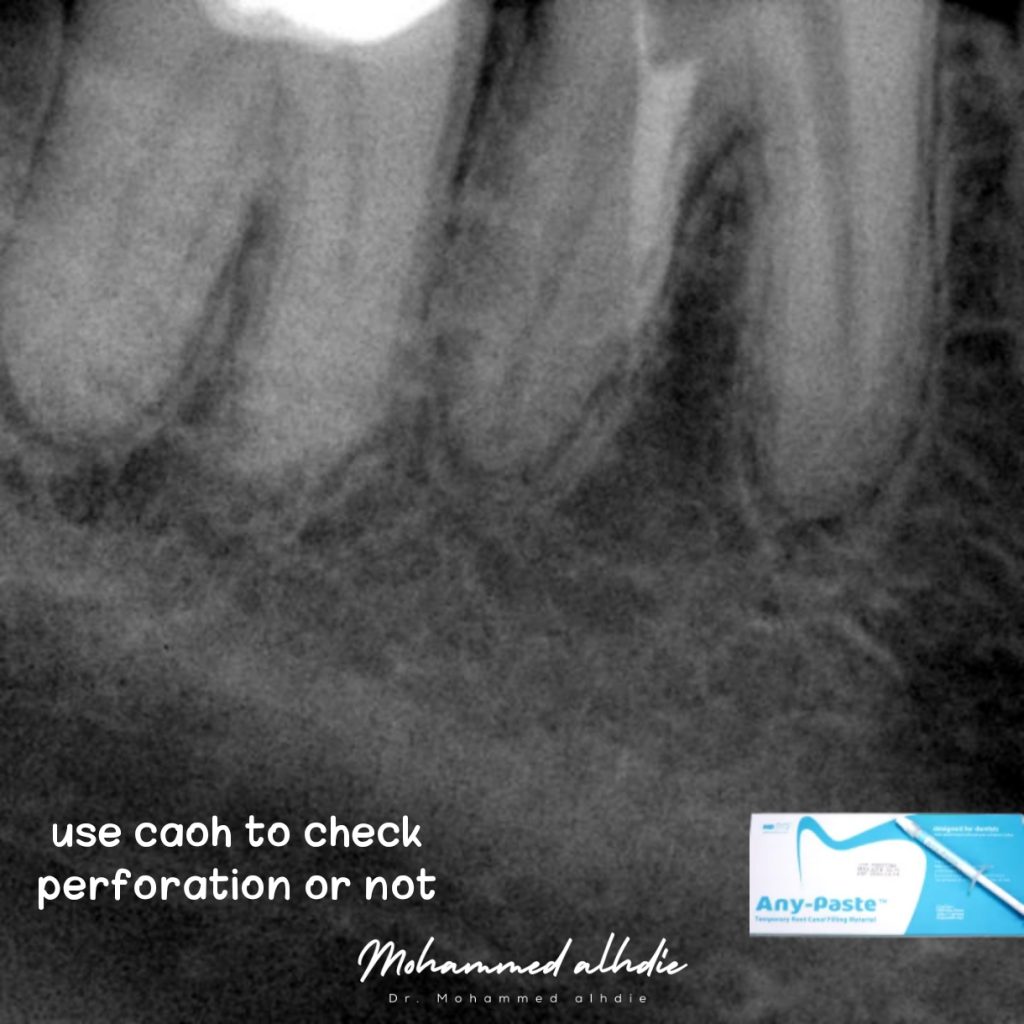

الصورة رقم 6: استخدمت caoh لفحص القناة أو الثقب (التوجيه) والمفاجأة أنها مثقوبة 😃